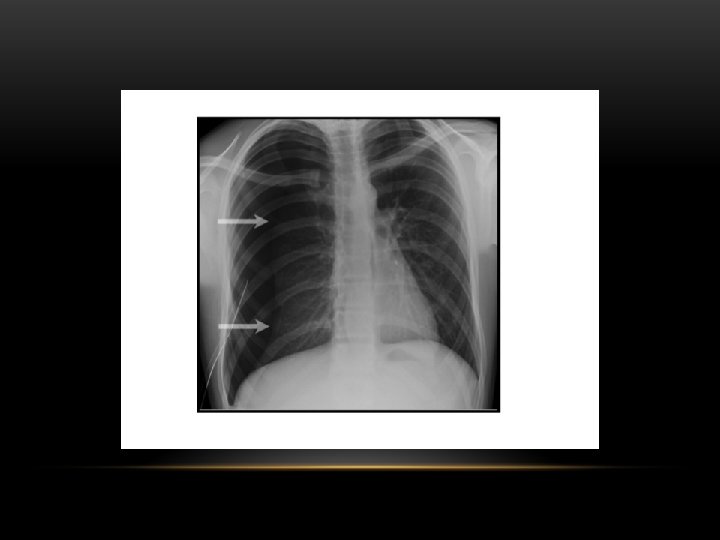

Pneumothorax is air in the pleural space. Radiological criteria: Air (black) in pleural space. No lung markings in pleural space. Recognition of atelectatic lung (lung margin). The lung recoils to a resting state as the negative pressure in the pleura is lost (relaxation atelectasis).

Pneumothorax • No vascular markings on right • No shift of mediastinum to left • Atelectasis right lung • Increased haziness on left: Diversion of entire cardiac output • Small fluid level near costophrenic angle: Hydro pneumothorax

Spontaneous Pneumothorax • Air in pleural space • Lung margin • "Normal lungs": Note the radiolucency of atelectatic lung is the same as the opposite lung